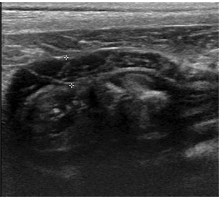

Sagittal ultrasonographic image of the stomach of a dog from the prospective study. The unorganized hyperechoic striations (UHS) are seen in the gastric muscularis layer (between the asterisks). This dog had no clinical sign related to the gastrointestinal tract

Ultrasonographic Features: UHS were more visible in the ventral gastric wall, especially when the stomach was empty or non-distended. When the stomach was distended with gas or fluid, the UHS appeared parallel to the serosa.

Histopathology: Among eight necropsied dogs with UHS, three had fibrous tissue within the gastric muscularis layer, suggesting a possible correlation with fibrosis. However, five dogs did not show increased fibrosis, indicating that other structural features, such as natural interfaces between the gastric muscularis sublayers, may contribute to UHS formation.